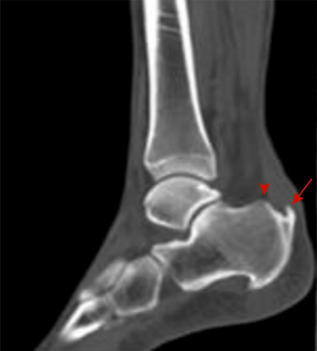

图4:X线检査可见跟腱止点处钙化增生(长箭头), 跟骨后上突增生(箭头)